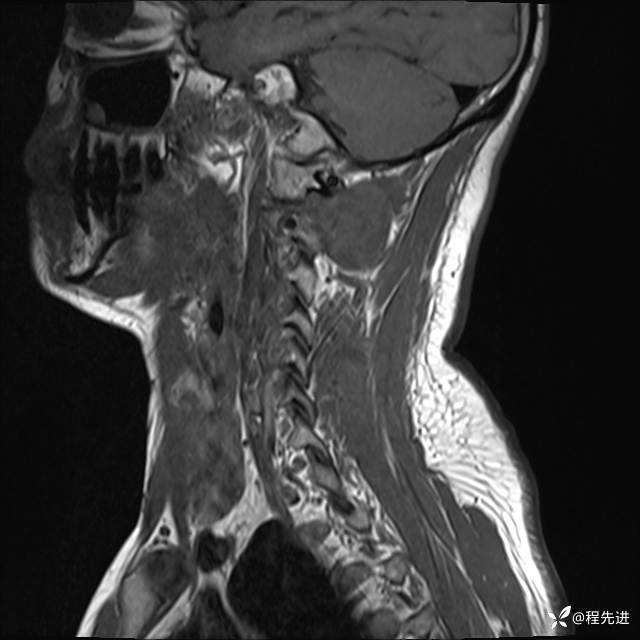

MRI平扫+增强:

T2:

T1:

T1增强: